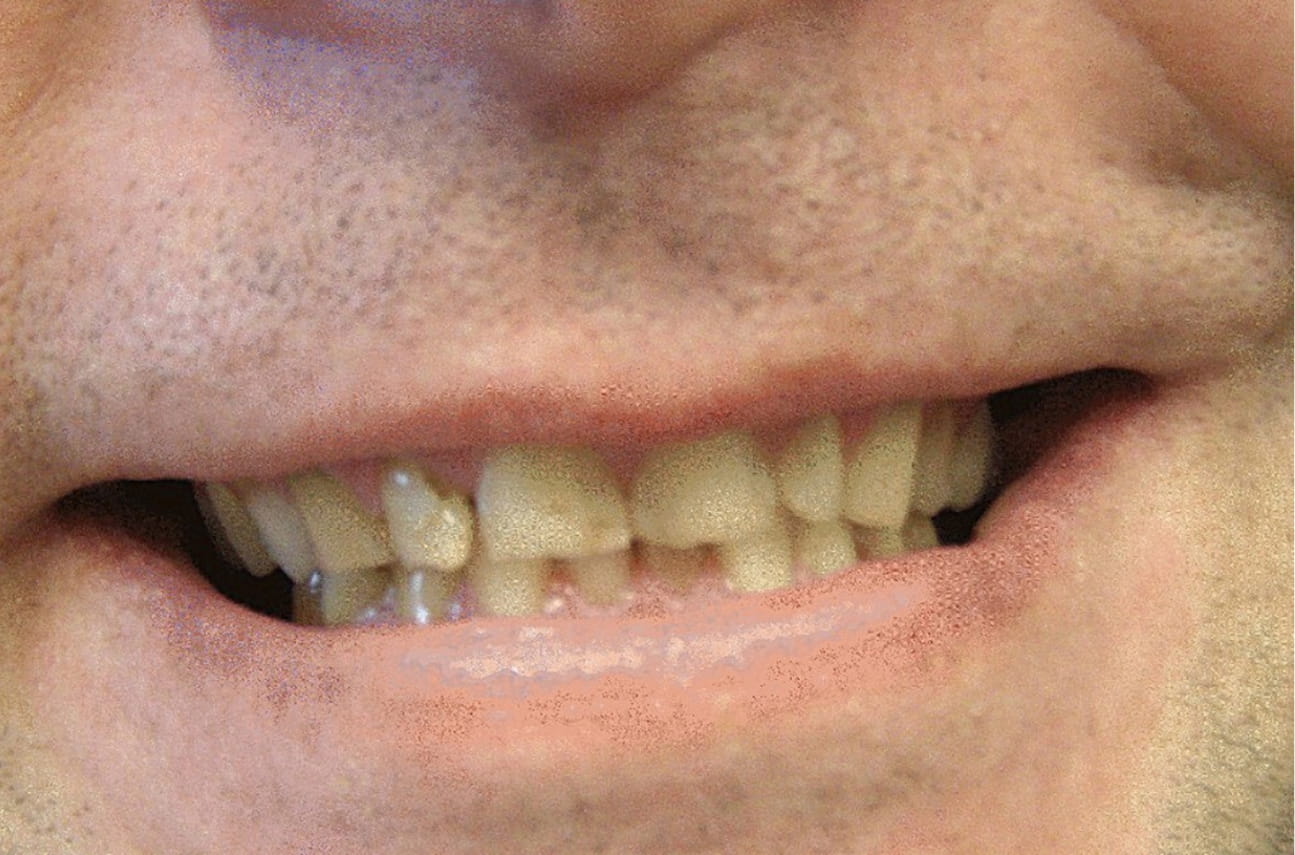

Grzegorz, 35 lat

Pan Grzegorz z Katowic, zgłosił się z prośbą o metamorfozę uśmiechu. Jego problemem był znaczny stopień zniszczenia zębów próchnicą, nieestetyczne przebarwienia na zębach, krzywy zgryz i nierówny kolor. Po wstępnej fazie higienizacyjnej przeprowadzono niezbędne do uratowania zębów leczenie zachowawcze a następnie w leczenie ortodontyczne nakładkami Invisalign. Ostatecznie uśmiech zaopatrzono koronami pełnoceramicznymi wykonanymi na zębach własnych Pacjenta. Szczęśliwy Pacjent powiedział, że nareszcie może się uśmiechać bez skrępowania i jeść w pełnym komforcie.